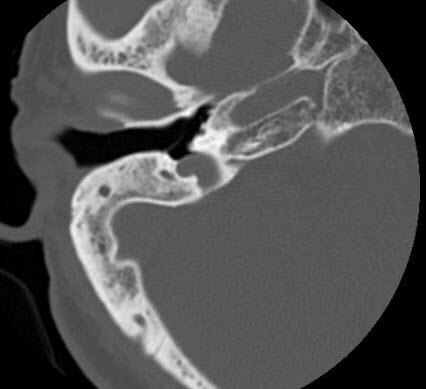

最近来自广东佛山汕头的黄女士,由于多年的鼓膜穿孔和鼓膜内陷,导致听力下降,耳鸣,非常的苦恼。一直觉得自己的鼓膜内陷了,又穿了孔,可能治不了。所以一直就拖着,几十年了,直到最近看手机,了解到佛山的耳鼻喉郑立岗医生可以做这种鼓膜内陷的耳内镜微创手术,就过来就诊了。

耳鼻喉郑立岗医生检查后确定黄女士的情况做耳内镜微创手术是没有问题的,就收住入院了。

这次做的是全麻耳内镜中耳炎微创手术,麻醉师插管全麻后就开始了手术,在耳内镜下不用做任何的体表切口,直接翻起外耳道鼓膜皮瓣,抬起内陷的鼓膜,听骨链是基本完整的,取合适大小的耳屏软骨修补鼓膜,鼓膜修补好后检查了两遍确认没问题后就结束了手术。整个的手术用时约80分钟,非常的顺利。术后查房患者无明显的不适,无手术相关的并发症。

对于鼓膜内陷伴鼓膜穿孔的中耳炎患者,耳内镜微创手术是可以解决的,这种手术的技术难度比较大,对医生的技术和经验要求非常高